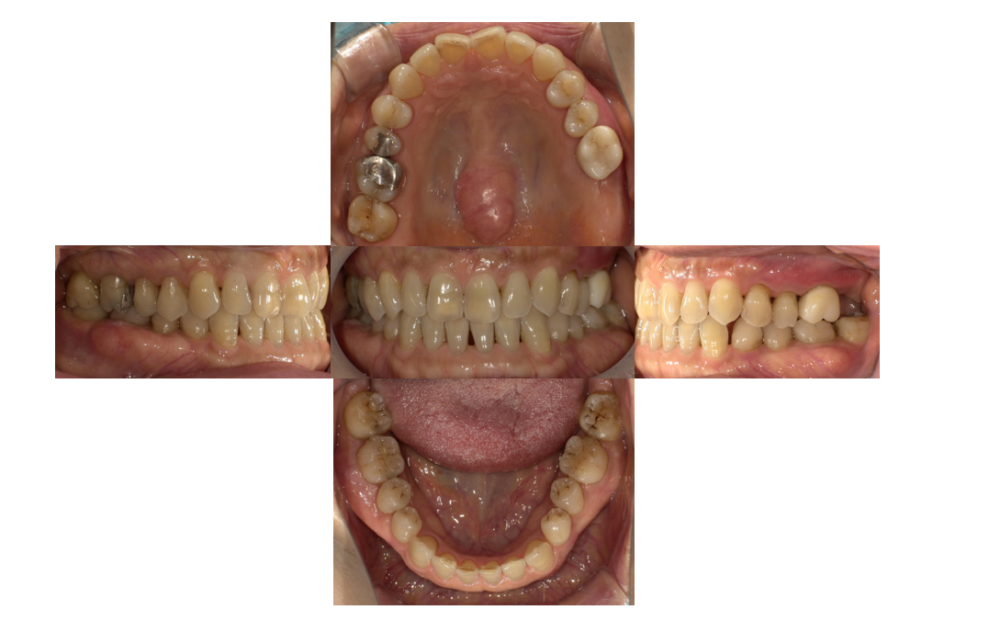

症例1

治療前

| 主訴 | 歯を入れたい |

|---|---|

| 診断 |

左下6残根 |

| 治療内容 | 左下6抜歯、インプラント補綴 |

| 年齢・性別 |

78歳、女性 |

| 治療期間 |

6ヶ月 |

| 治療費用 | 診査診断¥22000+インプラント一次オペ(京セラ)¥275000+GBR¥110000+上部構造(ジルコニア)¥143000 総額¥550000 |

| リスク・副作用 | インプラント周囲炎、インプラント上部構造の緩み |